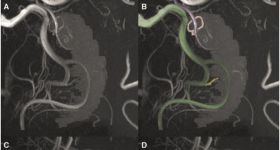

內(nèi)側(cè)顳葉相關(guān)的認(rèn)知功能極易受海馬區(qū)域缺氧影響,然而海馬血管供應(yīng)情況與認(rèn)知之間的關(guān)系我們?nèi)灾跎?。海馬...